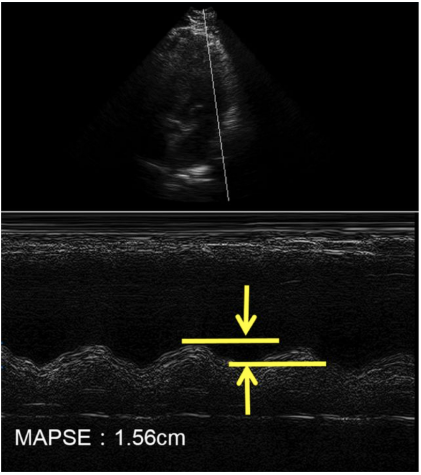

(3)二尖瓣瓣环收缩期位移/长轴缩短量(MAPSE):和三尖瓣TAPSE一样,在心尖四腔心切面,使用M超,瞄准外侧二尖瓣根部,追踪位移水平(图23)。MAPSE的参考值为大于1.3 cm。

图片

图23. M超测量MAPSE